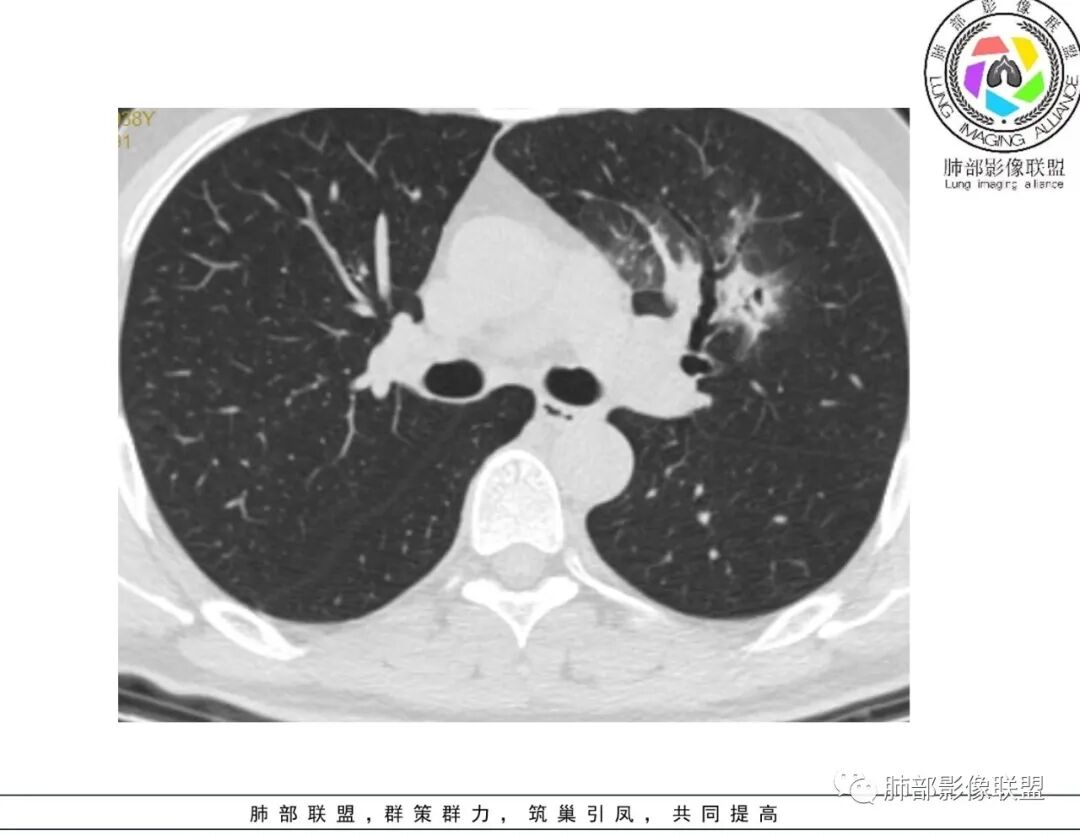

谢加平:左肺上叶和右肺下叶见多发散在性斑块病灶,边界清楚,部分见U形凹陷和刀切征,周围见模糊晕征,近胸膜下分布和蘑菇兄弟特点,累及左肺上叶上舌段支气管牵拉性扩张,前后13天复查整体病灶吸收不明显,有机化趋势表现,首选炎性肉芽肿(隐球菌感染?),请结合隐球菌荚膜抗原检查。

蓝天白云:两肺多发斑片状影,晕,内见扩张支气管影,可见直边,轻度延迟强化,纵隔肿大淋巴结,考虑炎性肉芽肿,隐球,淋巴瘤。

尘缘:中年男性,咳嗽咳痰伴乏力多汗,无发热,偶有畏寒。期间至某中医院治疗服中药后,症状好转。白细胞与血沉稍高。影像表现:左上肺团块状影(增强后CT值约22,伴有血管漂浮),中间支气管明显扩张,伴有小空洞形成,周围有晕,右下肺多发团块状影(增强后CT值约48),无明显支扩,伴胸膜下多发小结节,13天后复查,左上肺主病灶无明显变化,其他病灶范围有缩小,空洞消失,右下肺病灶变化不明显。

傅昌瑜:青年男性,咳嗽咳痰3周。白细胞计数稍升高,CRP正常。两肺多发斑片状、结节影,周围见边缘模糊磨玻璃影,部分边缘见毛刺,支气管穿行稍扩张。治疗后(具体药物不详),周围磨玻璃影减少,病灶似乎变小。无明显发热、白细胞无明显升高、CRP正常,治疗10天后复查吸收不明显,不支持细菌性肺炎。无发热、鼻窦疾病及血尿(未提供相关检查)等,血管炎可能性不大。肺内病灶形态单一类似、无树芽征,不支持肺结核。综合考虑隐球菌可能性大,鉴别淋巴瘤、血管炎。

2、影像资料:双肺多发的小结节、斑片状及不规则型的实性病灶,周围有晕,沿支气管血管束分布,部分的病灶周围可见磨玻璃样影、支气管的扩张以及小的空洞。增强扫描病灶,轻度强化内部见支气管造影征。部分的病灶,支气管有扩张,内壁凹凸不平的改变,纵隔淋巴结未见肿大。病灶整体的形态还是多样化,部分位于胸膜下。

3、治疗:经氟康唑治疗2周后,影像上以边缘的磨玻璃样病灶的吸收为主。